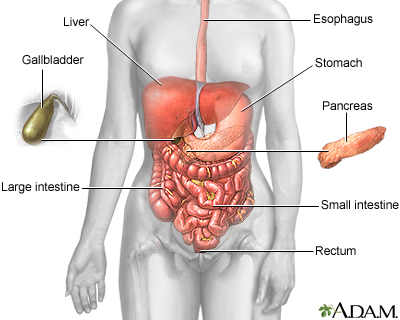

Heartburn is a painful burning feeling just below or behind the breastbone. Most of the time, it comes from the esophagus. The pain often rises in your chest from your stomach. It may also spread to your neck or throat.

Normally when food or liquid enters your stomach, a band of muscle at the lower end of your esophagus closes off the esophagus. This band is called the lower esophageal sphincter (LES). If this band does not close tightly enough, food or stomach acid can back up (reflux) into the esophagus. The stomach contents can irritate the esophagus and cause heartburn and other symptoms.

Heartburn is more likely if you have a hiatal hernia. A hiatal hernia is a condition which occurs when the top part of the stomach pokes into the chest cavity. This weakens the LES so that it is easier for acid to back up from the stomach into the esophagus.